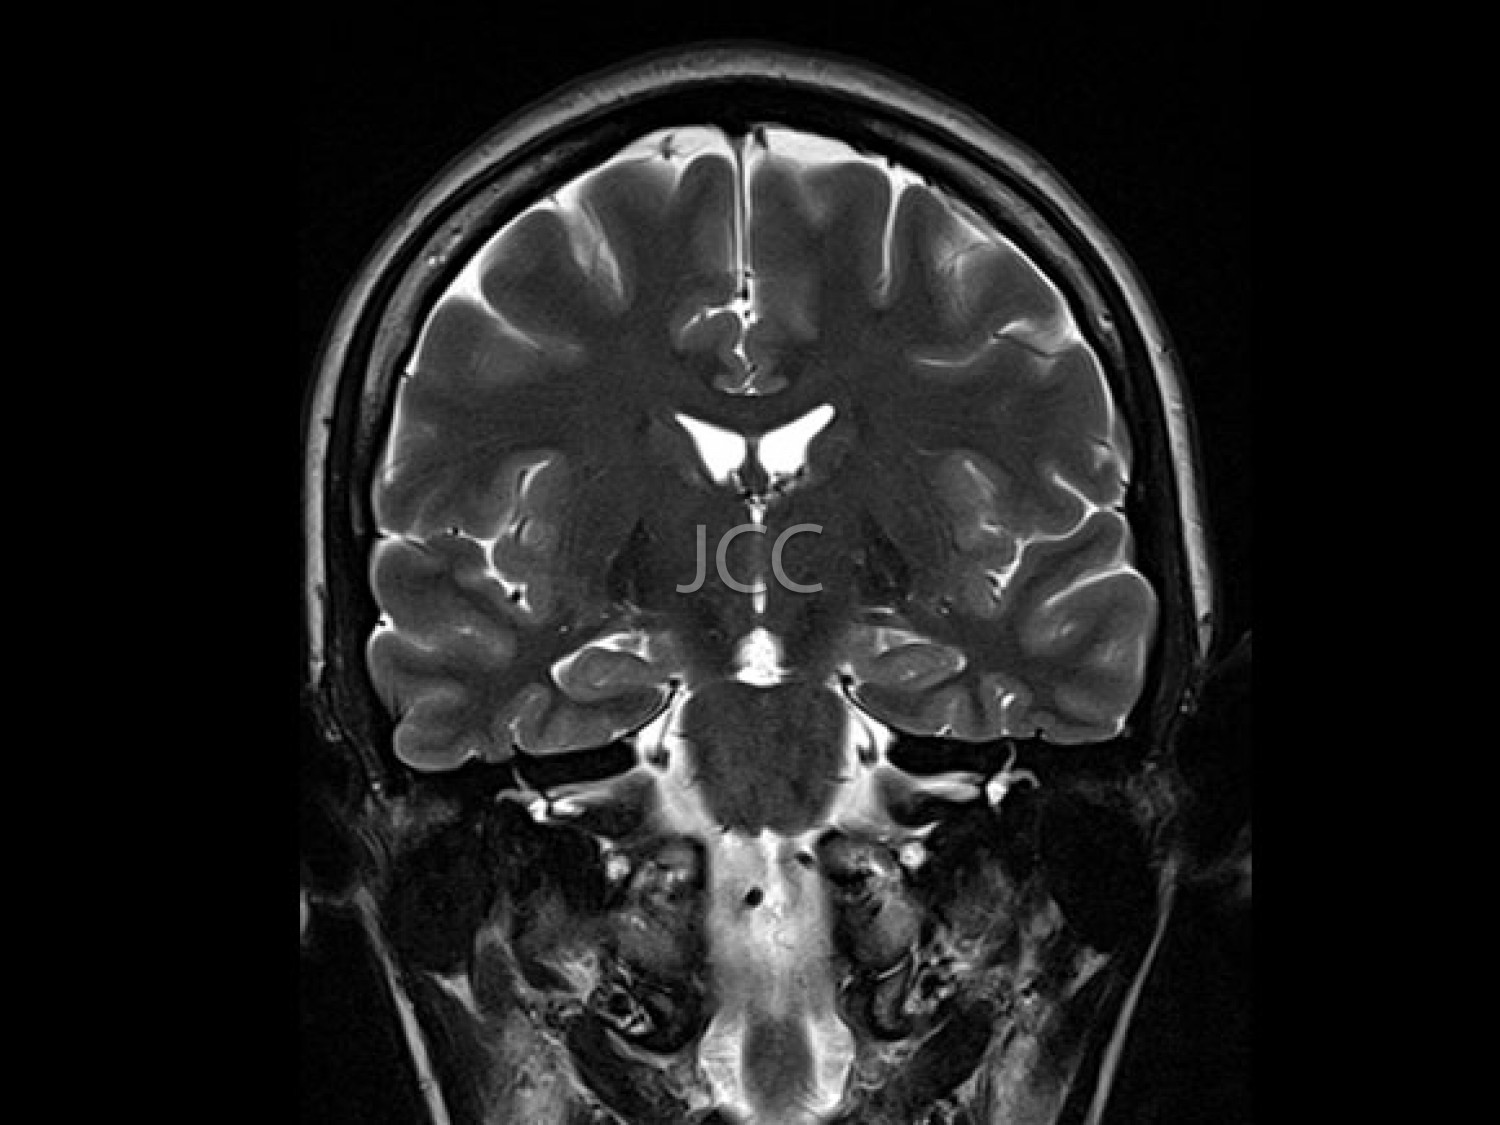

A angiografia das carótidas por TC, utilizando tecnologia de alta resolução e baixa dose de radiação, constitui o método não invasivo mais apurado, na avaliação das artérias carótidas e vertebrais, ou seja, as artérias que transportam o sangue para o cérebro. A redução do calibre por deposição de colesterol (placas) das carótidas e artérias vertebrais, é facilmente demonstrada por este método, bem como eventuais aneurismas das artérias cerebrais. A ressonância magnética permite a correcta demonstração e caracterização das malformações vasculares cerebrais, bem como a detecção precoce de inúmeras outras patologias cerebrais.